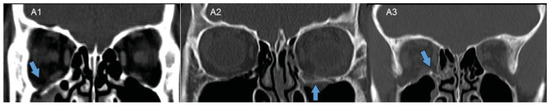

| Fracture extent, n (%) | |||

| A1 | 2 (40.0%) | 16 (37.2%) | 0.52 |

| A2 | 2 (40.0%) | 13 (30.2%) | 0.47 |

| A3 | 1 (20.0%) | 14 (32.6%) | 0.55 |